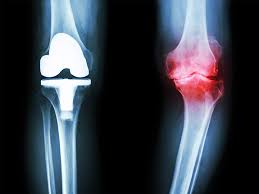

Reclaim Your Mobility: Local Joint Pain Relief ...